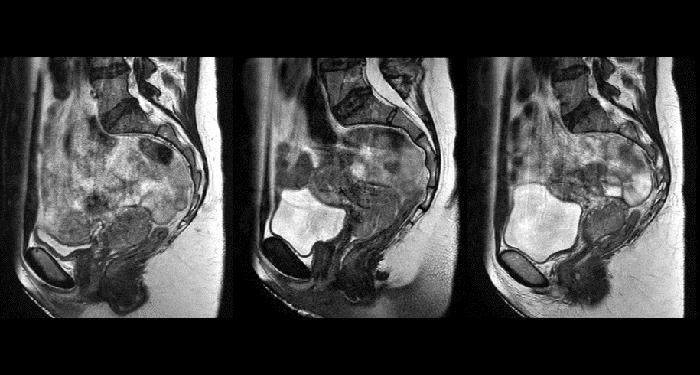

With its exceptional soft-tissue visualization capabilities and wide range of image contrasts, MRI has become a powerful tool to help more precisely define tumor boundaries. This is particularly important as it has been established that there is a high degree of uncertainty in target volume delineation, and it is even reported to represent the largest uncertainty in the entire radiotherapy process for most tumor sites**. Better visualization of the target area and nearby organs-at-risk is a key factor in enhancing target volume delineation. MRI’s expanding role also can be attributed to its functional imaging capabilities, which can inform both target characterization and treatment response.

With its superior soft tissue contrast compared to CT, MRI offers exquisite visualization of tumor boundaries and proximity to nearby critical structures.

Unlike CT, MRI images are created without using ionizing radiation. This is particularly important when the patients are children, in which exposure to a radiation dose should be minimized to reduce long-term secondary effects. The option to acquire multiple MRI exams paves the road towards “plan-of-the-day” approaches or monitoring treatment response for adaptive strategies.